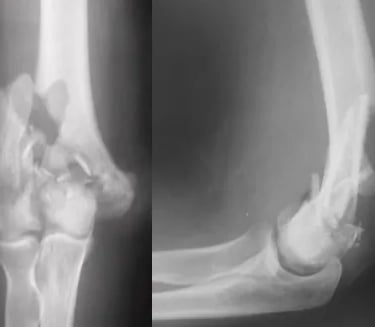

Fratura Distal do Úmero

O úmero, o osso do braço, articula-se com a ulna e o rádio no cotovelo. As fraturas da porção distal do úmero costumam ocorrer após queda ao solo. Esta é a fratura mais grave dentre as que podem acometer o cotovelo.